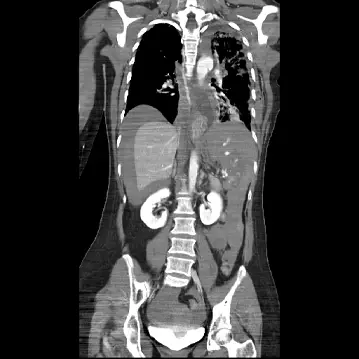

影像分析:

- 腹部 axial CT:大量高密度腹腔游離液(血液);右上腹肝實質裂傷伴 contrast extravasation,周圍血塊形成,為持續性主動出血影像。

- 腹胸冠狀面重組:更清楚顯示肝右葉深度裂傷及主動對比劑外滲,血腔沿腹腔、盆腔擴散;橫隔以下血量明顯多於胸腔,支持腹內出血為主要休克來源。